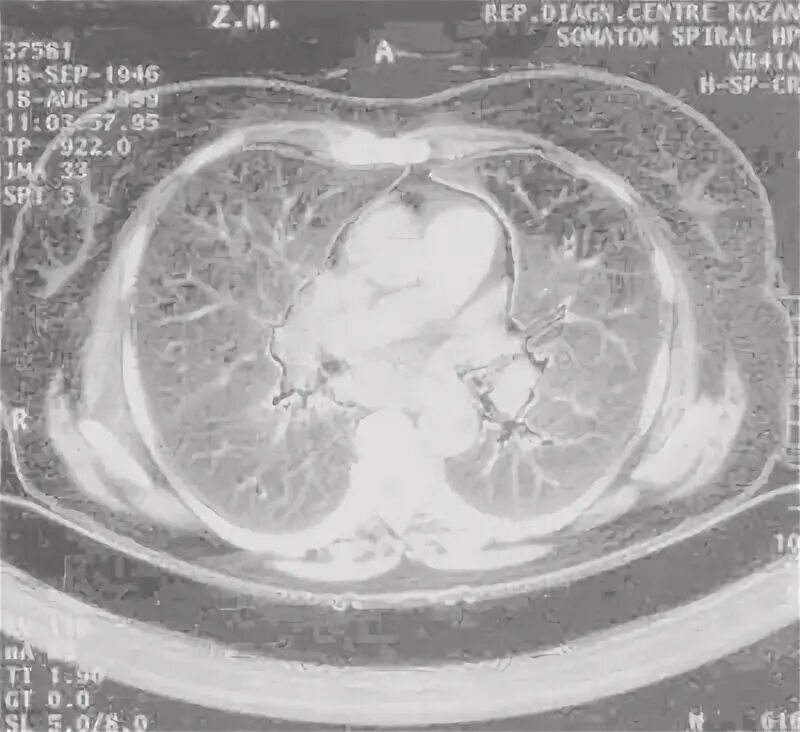

Саркоидоз код по мкб 10 у взрослых